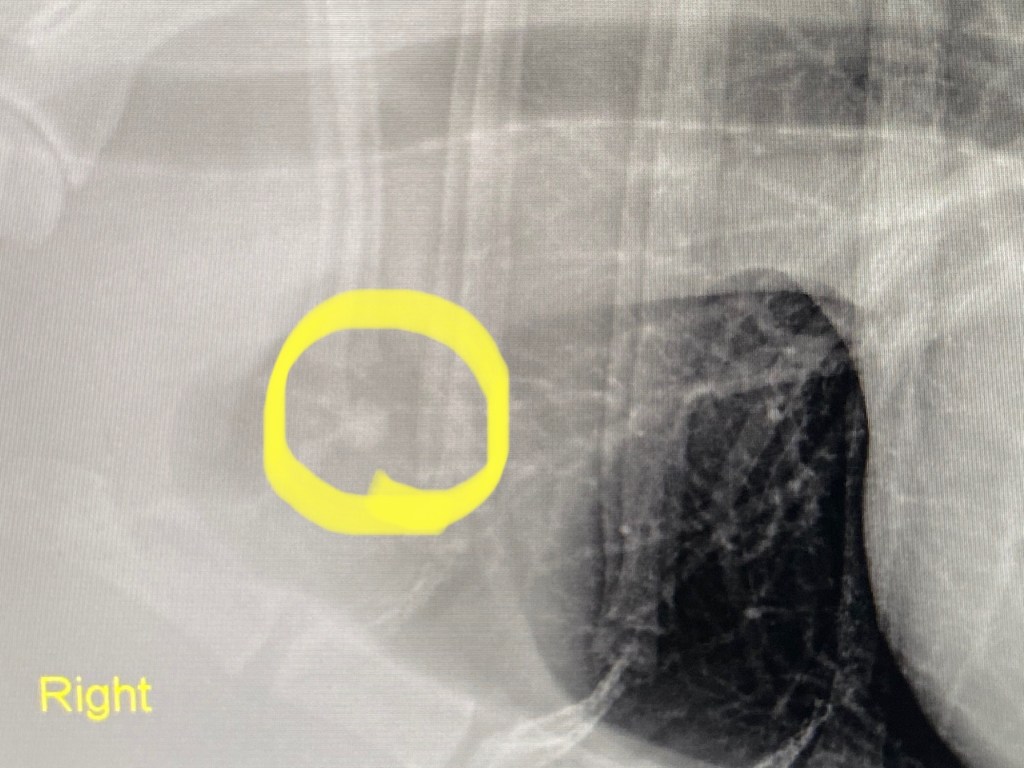

I had our vet take another set of chest X-rays. Unfortunately, they show an ominous spot on his lung that wasn’t there in the last two X-rays taken in January and March. This is really soul-crushing news. Campy had been doing so well up until now.